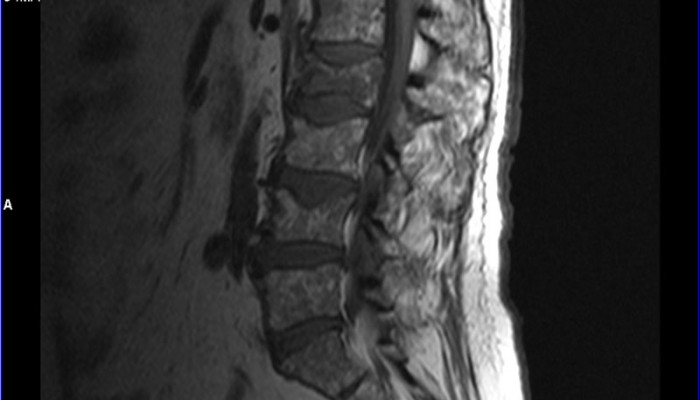

Для подтверждения гидромиелии используют миелографию и компьютерную томографию, однако информативным и надежным методом диагностики этого заболевания является магнитно-резонансная томография.

На МРТ можно обнаружить гидромиелические полости. Обычно они достигают небольших размеров в диаметре – от 0,2 до 0,4 см и заполнены ликвором. Поперечник спинного мозга на этом уровне не расширен.

При гидросирингомиелии на МРТ будут также видны веретеновидные полости, заполненные ликвором и не накапливающие контрастное вещество. Поперечник спинного мозга на этом уровне расширяется.